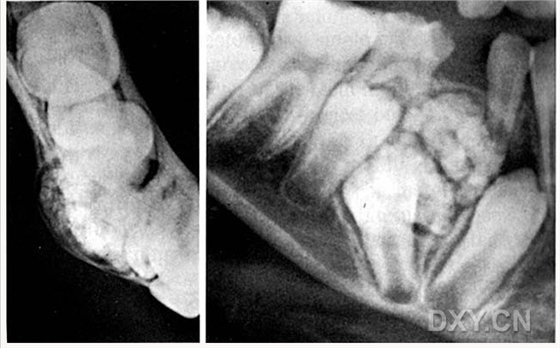

涎石病

球狀上頜囊腫

含牙囊腫

球狀上頜囊腫    含牙囊腫